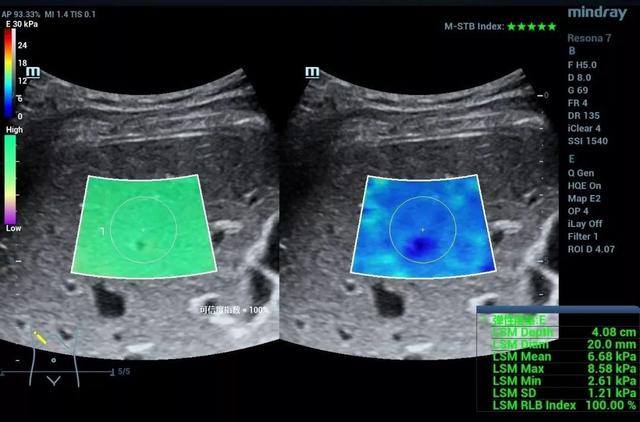

作为一种无创的能够反应组织硬度的功能性成像方法。目前剪切波弹性成像的研究已经涉及肝脏、甲状腺、乳腺、胃肠道、肌骨等方方面面,对于弥漫性病变的分级、局灶性病变的鉴别诊断、疾病的监测及随访等都有重要的意义。例如诊断肝脏纤维化的分期,从F1-F4的图像中,我们发现,尽管二维声像图差别不大,但当纤维化程度增高时,肝脏杨氏模量也增高了,也就是说肝脏“变硬”了。可见,超声发展到这里,不但有形态学上的灰阶超声,血流动力学上的彩色多普勒超声,还有机械力学上的弹性超声。

肝纤维化F1期

肝纤维化F2期